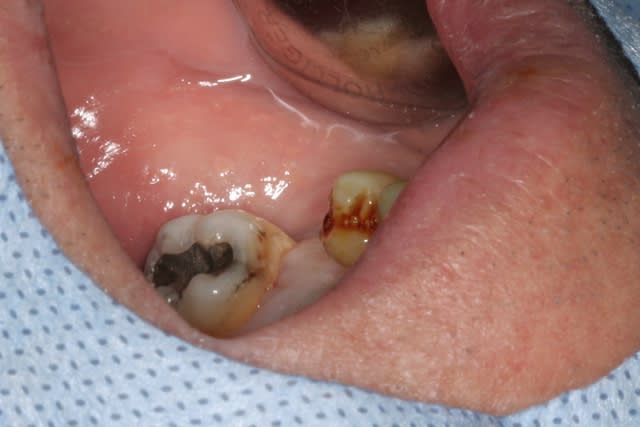

oh le cas clinique n'a rien de bien exceptionnel....une 36 à remplacer, par contre il est vrai avec une largeur de crête de folie (de mémoire je dois avoir 15mm!!!), une bonne douzaine de mm en prenant de la marge au dessus du NDI dans un os qui est cicatriciel (extraction il y a 5 ou 6 mois, je ne sais plus exactement) donc certainement D2 / D3, 10/11mm entre la 5 et la 7....bref: autoroute...

naturellement, un 5/11.5 va tranquillement y prendre place...;-)